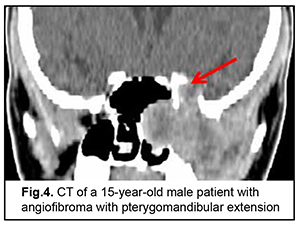

Cerebral and focal neurologic complaints were the most common type. In addition, these complaints were almost as common in patients with benign ASBOT (39.8%) and in those with malignant ASBOT (40.9%) (р > 0.05). Headache, dizziness, fatigue, general weakness, and somnolence were classified as cerebral complaints. Focal neurologic symptoms included facial numbness (impaired CN 5 function) in 15 patients, facial asymmetry (CN 7 dysfunction) in 5 patients, impaired swallowing and phonation (caudal nerve dysfunction) in 3 patients. The severity of cerebral and focal neurologic symptoms depends on the degree of intracranial extension of the lesion and potential cerebral edema. Of note that intracranial hypertension was observed only in patients with significant cerebral edema. Difficulties with nasal breathing, purulent nasal discharge, and epistaxis (due to tumor obstruction of the natural foramina between sinuses and consequently impaired natural ventilation of the nasal cavity and paranasal sinuses) were classified as rhynologic complaints. There was no significant difference in the frequency of these complaints between patients with benign ASBOT (28.7%) and those with malignant ASBOT (27.1%) (р > 0.05). A progradient course of rhynologic symptoms was a feature of our patients with ASBOT. Rhynologic complaints did not improve, but increased in severity with time. It should be noted that, in the current study, epistaxis was occasional and mostly in patients with nasopharyngeal angiofibroma. Reduced visual acuity, diplopia, oculomotor abnormalities, ophthalmoplegia, exophthalmos, tearing, eyelid swelling and chemosis and ocular pain were classified as neuroophthalmologic complaints. Neuroophthalmologic complaints and the third most common type of complaints, and were caused by extension of the craniofacial lesion into the orbit. In addition, these complaints were almost as common in patients with benign ASBOT (21.3%) and in those with malignant ASBOT (25.9%) (р > 0.05). Otologic complaints were the least common in our patients with ASBOT. They included hearing loss, noise, and stuffy ear, and were caused by eustachian tube obstruction and expansive tumor growth or tumor-associated inflammation. Another cause was expansion of the tumor to middle and inner ear structures with their subsequent destruction and hearing loss. Otologic complaints were common in patients with benign ASBOT (10.2%) than in those with malignant ASBOT (6.1%), but the difference was not significant (р > 0.05). It should be noted that the frequency of rhynologic complaints caused by rapid expansion of the tumor in the nasal cavity or orbit and periorbital growth was almost the same as the frequency of rhynologic complaints due to these causes. Patients with benign ASBOT had practically the same complaints as patients with malignant ASBOT, and the severity of these complaints mostly depended on lesion extension and tumor growth duration. Most patients with benign and malignant PELGT had complaints associated with nasal displacement of the globe by the newly formed tissue at the superior and outer surface of the upper eyelid (the lacrimal gland area) and limited upward and outward movement of the globe (53.8% and 58.2% of cases, respectively). In addition, in most patients with benign and malignant PELGT, the tumor mass was dense (92.2% and 96% of cases, respectively), the tumor surface smooth (72.6% and 66.1% of cases, respectively), the tumor mass immobile with respect to the bony orbital walls (66.6% and 83.0% of cases, respectively). The following clinical signs were found significant for differentiating a malignant from a benign PELGT: ptosis (Δ%=15.8, р=0.04), conjunctival hyperemia (Δ%=21.6, р=0.01), diffuse pattern of tumor growth (Δ%=21.5, р=0.05), impossibility of globe reposition (Δ%=22.3, р=0.03), and pain in palpation of the tumor (Δ%=9.4, р=0.04). Benign ASBOT Jjuvenile nasopharyngeal angiofibroma grows slowly, but tends to recur and/or grow into the structures adjacent to the epipharynx and nasal cavity, which may seriously complicate tumor excision. There was CT and MRI evidence that the tumor exhibited sphenoethmoidal and pterygomandibular patterns of growth (Figs 3, 4). An angiofibroma grows in an asymptomatic way extradurally through expanded natural foramina of the middle skull base, particularly, foramen ovale, foramen rotundum and fissura orbitalis superior. The tumor also exhibits extension into the cavernous sinus due to destruction of the lateral walls and floor of the sphhenoidal sinus. Initially, the tumor affects the pterygopalatine and infratemporal fossae, and, subsequently, expands to the cavernous sinus through the natural foramina of the middle skull base, particularly, foramen ovale, that becomes significantly expanded, foramen rotundum and fissura orbitalis superior. In addition, the tumor displaces the cavernous sinus, but becomes located extradurally, beyond the sinus. This is accompanied by symptoms of oculomotor nerve damage, reduced visual acuity due to destruction of the wall of the optic nerve canal and orbital cone, optic nerve compression and tumor mass filling the orbit, which was observed in this case. Patients with angiofibroma usually do not notice such symptoms as moderate headache and stuffy nose. Nasal bloody discharge and oculomotor abnormalities prompted suspicion for a nasal cavity tumor. This required additional examination (particularly, MRI of the brain) that led to finding the tumor.